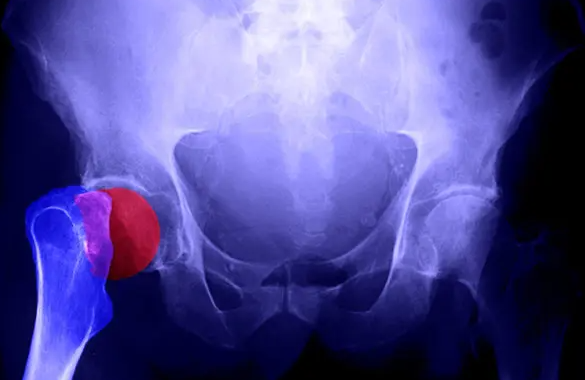

골다공증은 뼈의 밀도가 낮아져 쉽게 부러질 수 있는 상태를 말합니다. 이를 막기 위해 투여하는 골다공증 주사는 뼈의 손실을 늦추거나, 새로운 뼈 형성을 촉진하는 약제입니다. 보통 병원에서는 비스포스포네이트 계열 또는 파라티로이드 호르몬 유사체 등을 사용하며, 개인의 나이·성별·질병 경과에 따라 주사 종류와 투여 주기가 달라집니다.

골다공증 주사 부작용은 약물이 뼈 대사에 직접 작용하기 때문에 생길 수 있는 자연스러운 반응입니다. 일반적으로는 몸이 새로운 약물에 적응하는 과정에서 나타나는 ‘초기 반응’이며, 개인의 건강 상태나 체질에 따라 강도가 다릅니다.